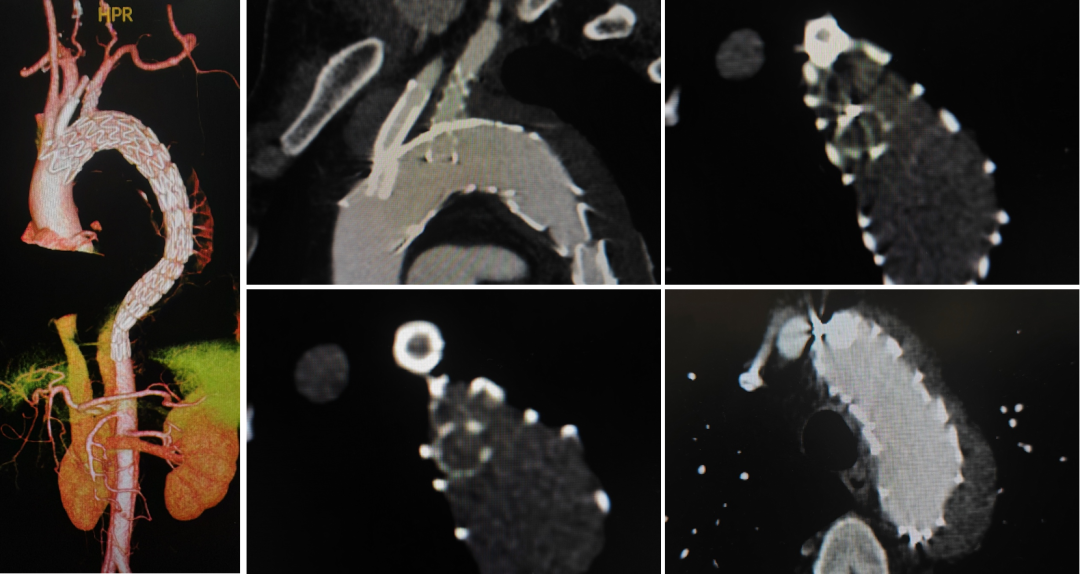

王X,男,57岁,主动脉弓动脉瘤。LSA、LCCA双内分支, IA开窗。

术前

术中